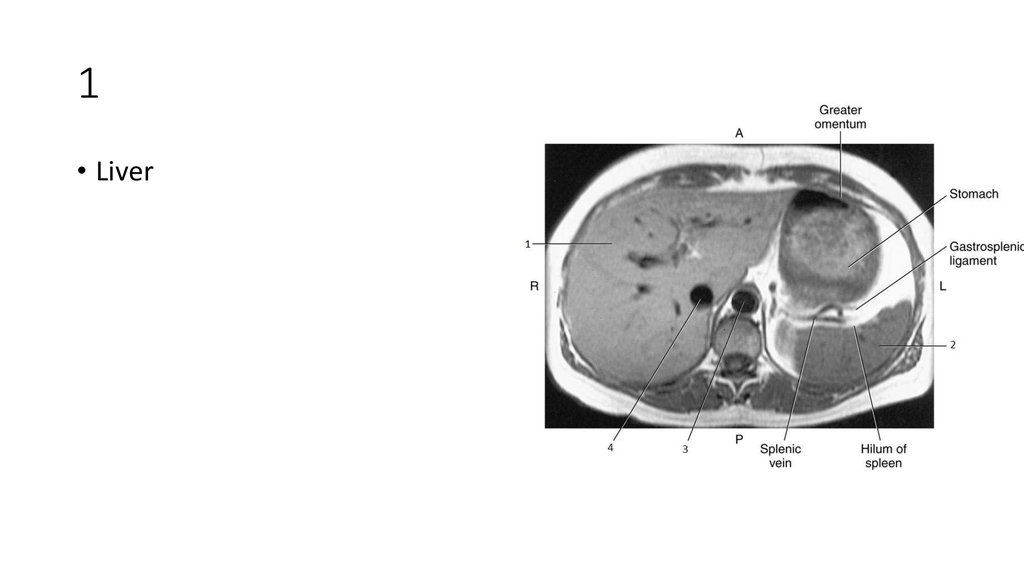

2. 1

3. 1

• Liver

4. 2

5. 2

• Spleen

6. 3

7. 3

• Aorta

8. 4

9. 4

• Inferior Vena Cava (IVC)